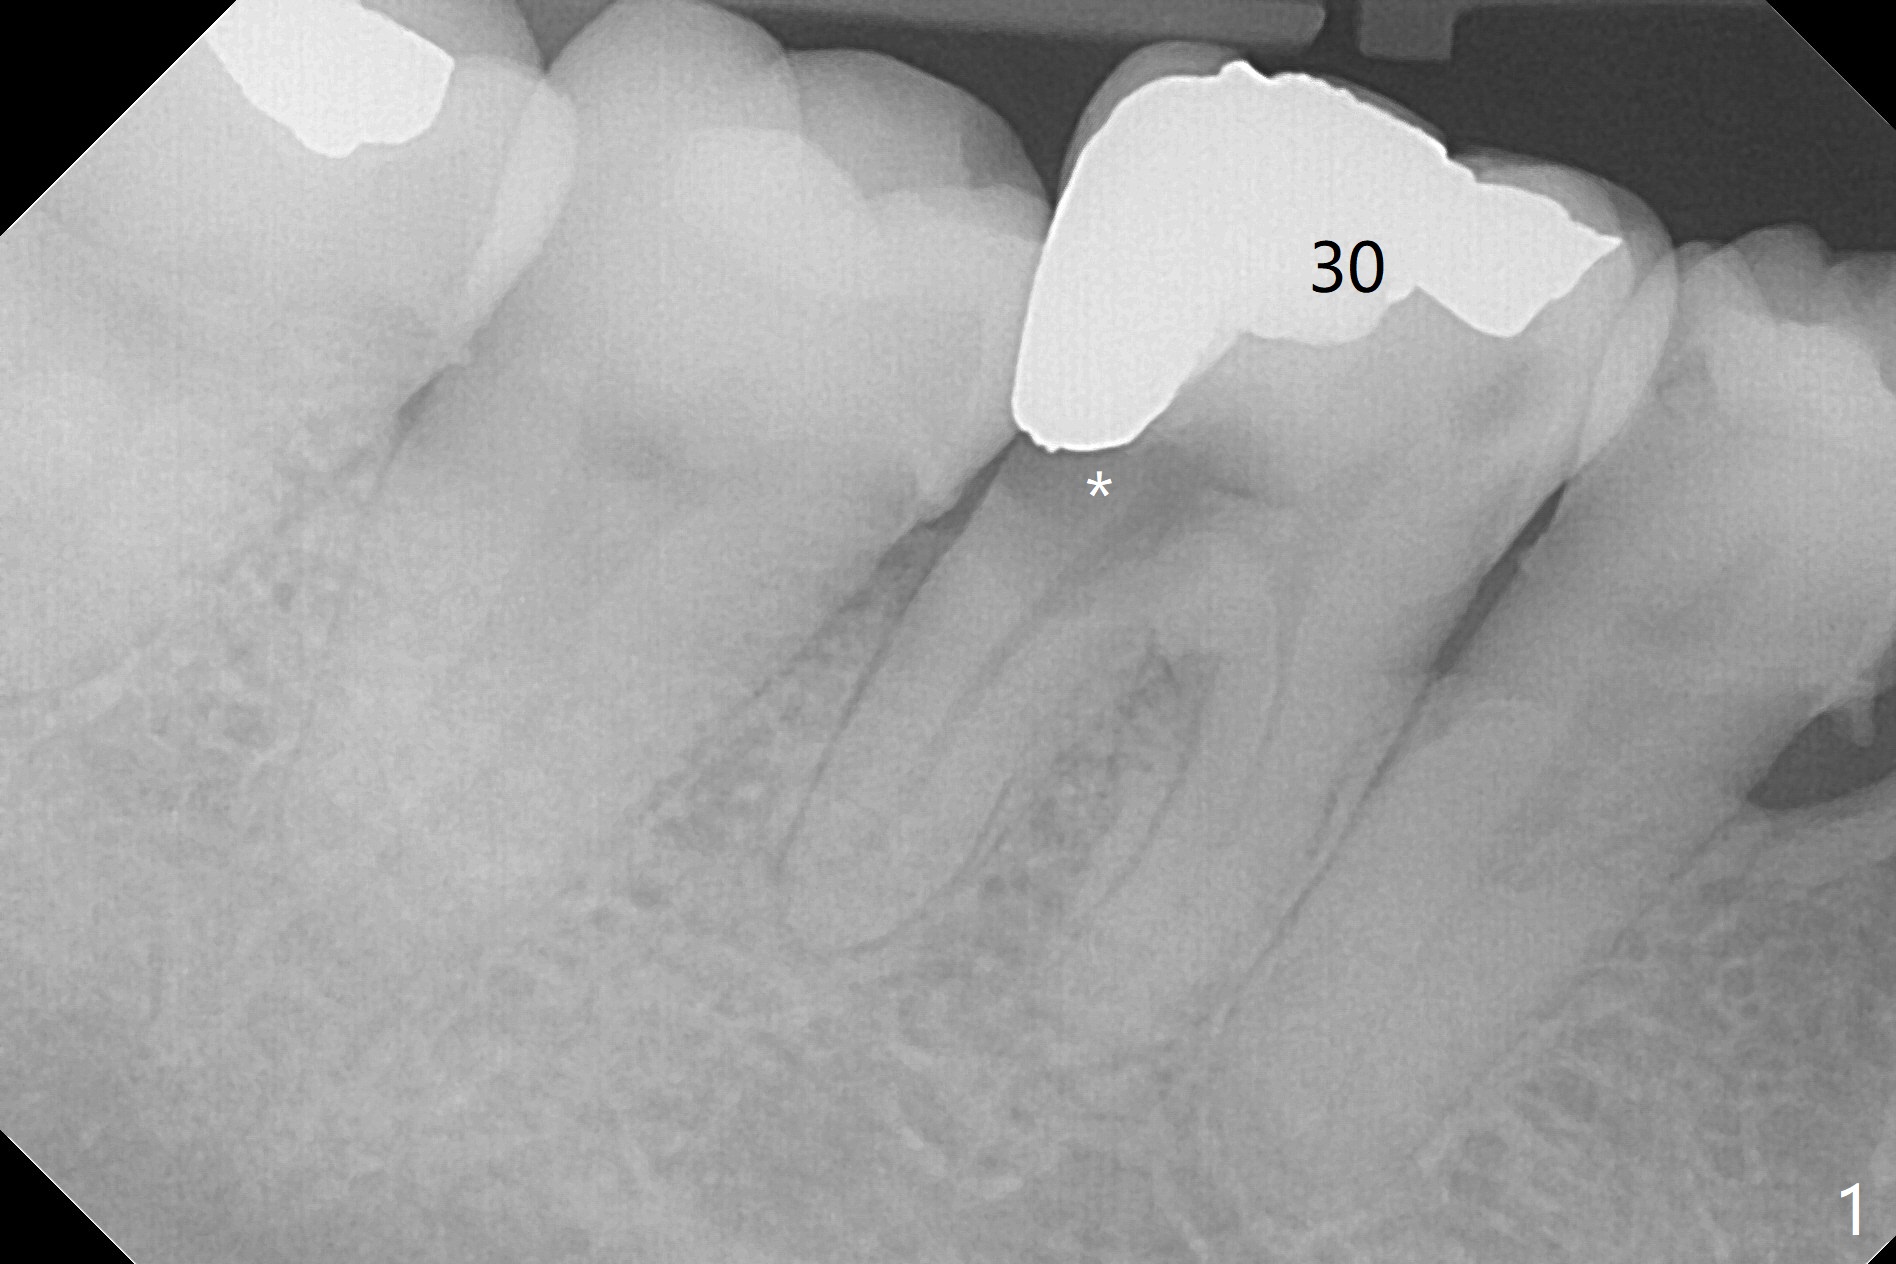

A 39-year-old woman has severe toothache associated with #30 subgingival caries (Fig.1 * distolingual). To reduce buccal plate perforation, a 4.5x11.5 mm implant will be placed (Fig.2 (bone height 15 mm). Take PA after parallel pin to make sure that blood supply to the tooth #29 is not compromised. For easy impression later, a temporary abutment will be used for immediate provisional so that a large soft tissue hemisphere is created. A cementation abutment is estimated to be 6.5x4(3) mm. Schedule SRP after implant placement (Fig.1). In fact the patient declines implant placement and accepts socket preservation (Fig.3 (*: Vanilla Graft)) because of history of hemorrhage associated with #19 extraction (Fig.4).